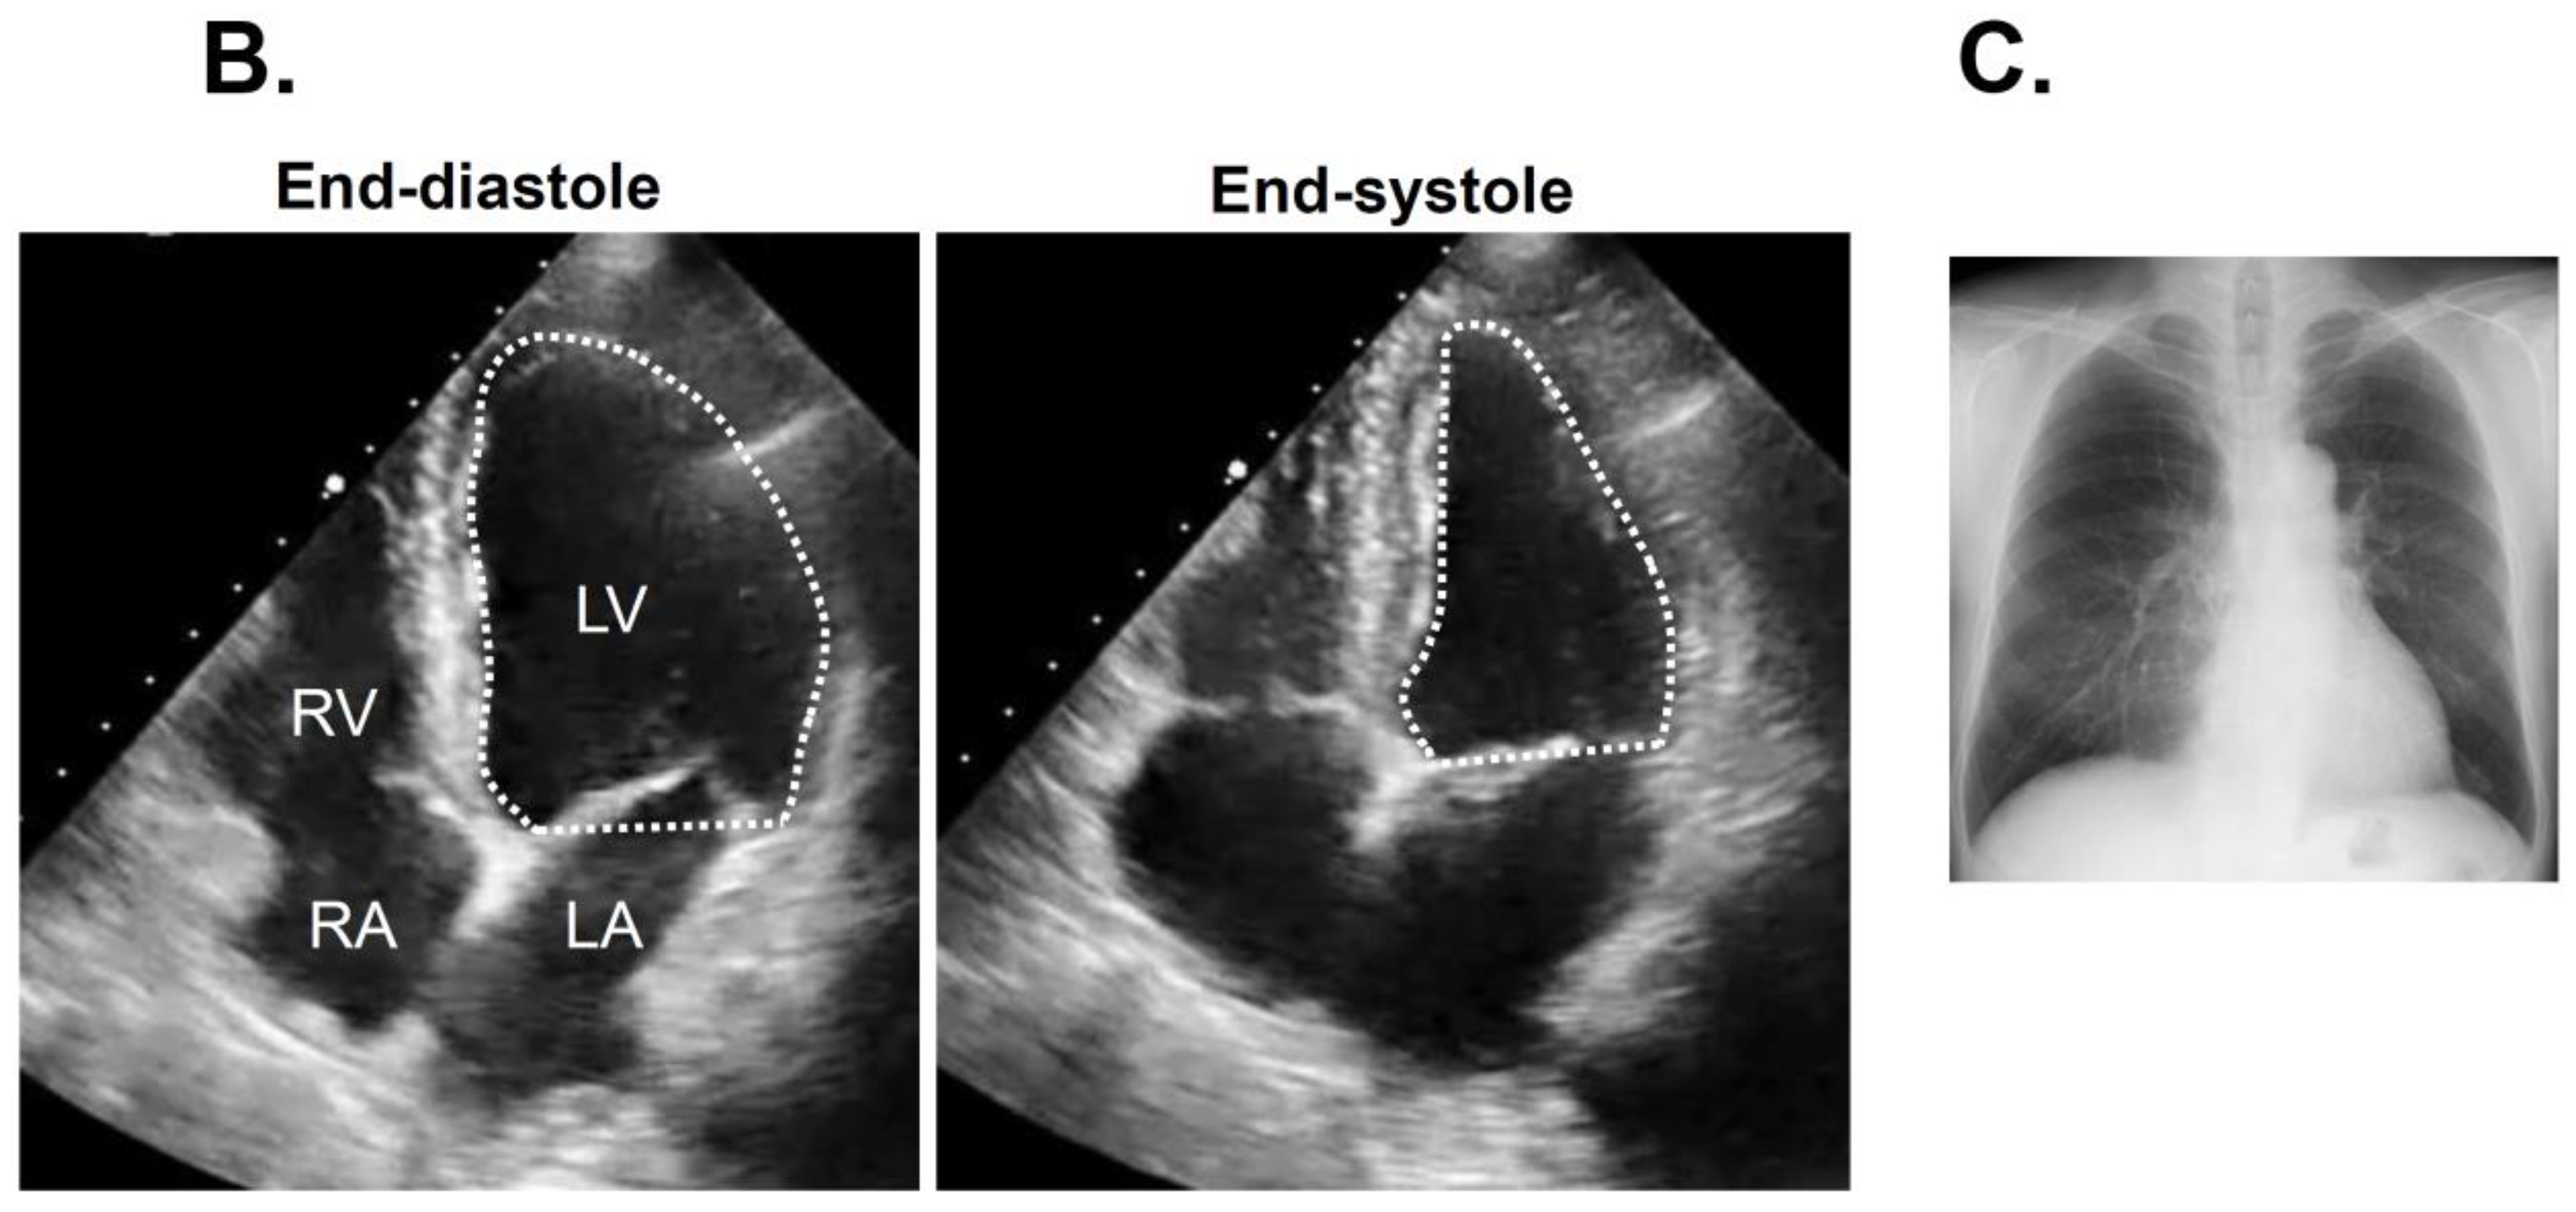

Electrocardiogram at index discharge showing sinus rhythm (A). Transthoracic echocardiography showing 65% of left ventricular ejection fraction (B) and chest X-ray with 45% of cardiothoracic ratio (C) obtained at three months following catheter ablation.

Following the index discharge, anti-heart failure agents remained unchanged. The post-procedural course was uneventful without any adverse events including the recurrence of atrial fibrillation. The patient was evaluated for AF recurrence by a clinical interview, electrocardiogram, and portable electrocardiograph (OMRON Corp., Kyoto, Japan) every month. New York Heart Association functional class was I with 21 pg/mL of plasma B-type natriuretic peptide at three-month follow-up. Transthoracic echocardiography showed 41 mm of left atrial diameter and 53 mm of left ventricular end-diastolic diameter (Figure 3B). Of note, left ventricular ejection fraction improved up to 65% without any wall motion asynergy. Chest X-ray showed 45% of cardiothoracic ratio (Figure 3C).